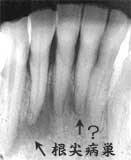

術前4年 Dental写真 2| Dental写真 同 口腔内写真

2|の知覚過敏を訴えるが異常は認められない 舌側は根尖に及ぶ歯槽骨吸収

72歳 女性

カリエスもなく舌側歯頚部部から排膿

口腔清掃状態はやや不良。全体に中程度以上の歯槽骨吸収が認められたが、年齢の割には比較 的良好ではあった。問題の下顎前歯部には、カリエスおよびカリエス治療の痕跡は見当たらない。

メインテナンス期間中にも所々カリエス進行に伴う追加処置を行ったが、全体としては特に問題 もなく順調に経過。2|については、4年前 ('96)に一度知覚過敏症状を訴えており、その時はレントゲン的に異常が認められず、薬剤塗布 により症状が消失し無事回復したものと思われていた。

そして今回、舌側の歯肉腫脹と排膿を伴う激しい炎症により、急激な動揺を伴った痛みにより、 緊急来院された。処置としては、通法に従い根管治療を行い消炎を確認しレジン充填にて歯冠 修復を行った。

考察:

結果からみると、4年前に知覚過敏を訴えた時点ですでに歯髄壊死があったものと思われる。 本性例に関して言えば、舌側歯槽骨の破壊が根尖部におよび“いかにも上行性歯髄炎”らしい 病態を示している。掲載したレントゲンでは不鮮明ではあるが、 2|の頬側および周囲歯の歯槽骨は 破壊の形跡は認められず、2|の舌側だけ が歯周疾患により破壊されたと考えるには不自然な状況である。